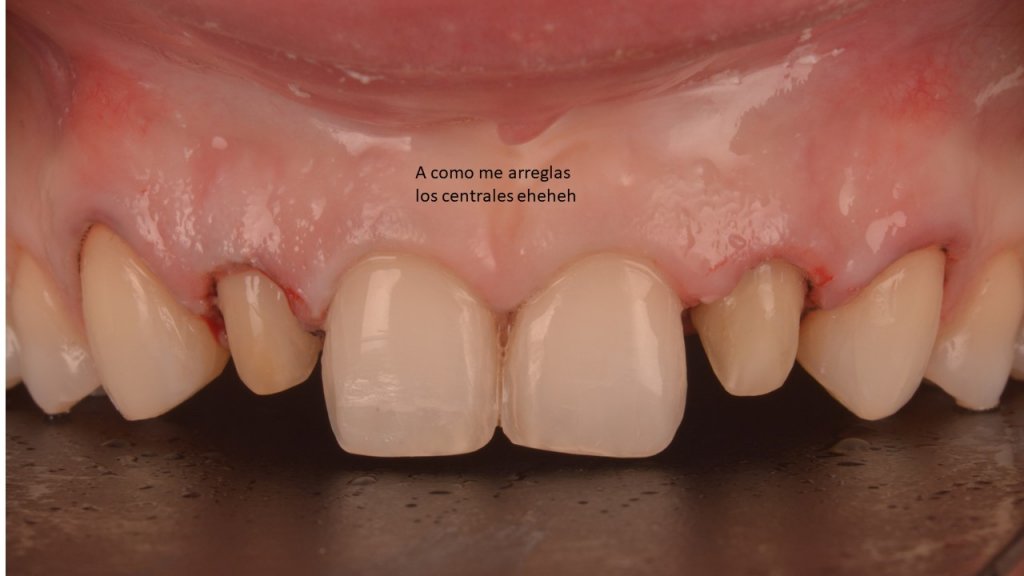

Antes de la retirada había alargado los dientes a través de una cirugía «semiabierta», para regularizar el festoneado gingival:

El inconveniente es que la encía, con un torque ridículo lingual de la raíz y la carilla desadaptada, volvía continuamente a bajar al no tener soporte.

Todos sabemos que el Mock-up es fundamental para revisar cositas y mejorar el resultado. Pero en este caso decidí utilizarlo también como soporte para estos dos cenits «recidivantes»